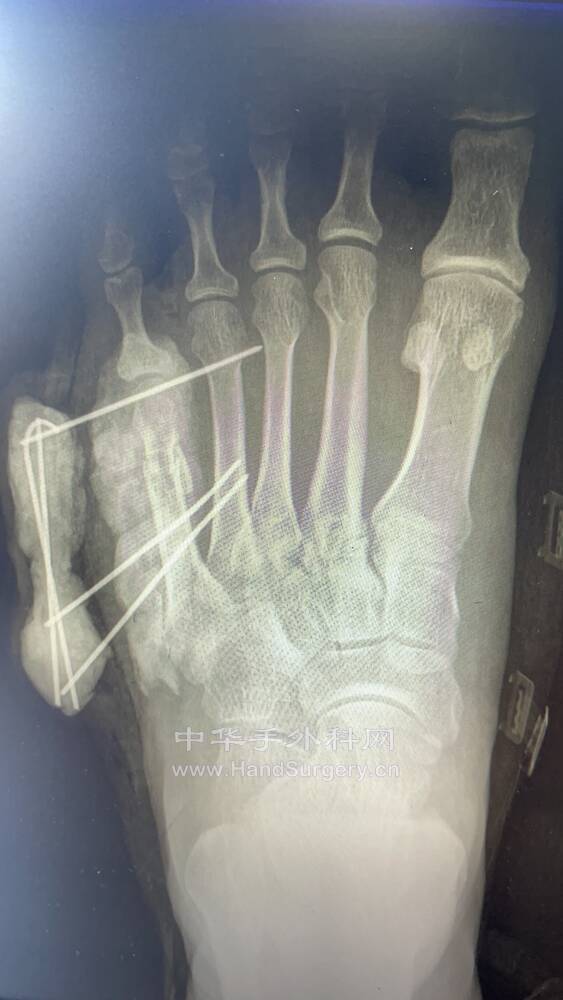

mmexport1628470422479.jpg

mmexport1628470404142.jpg

mmexport1628470410598.jpg

饺子粉+克氏针妙用